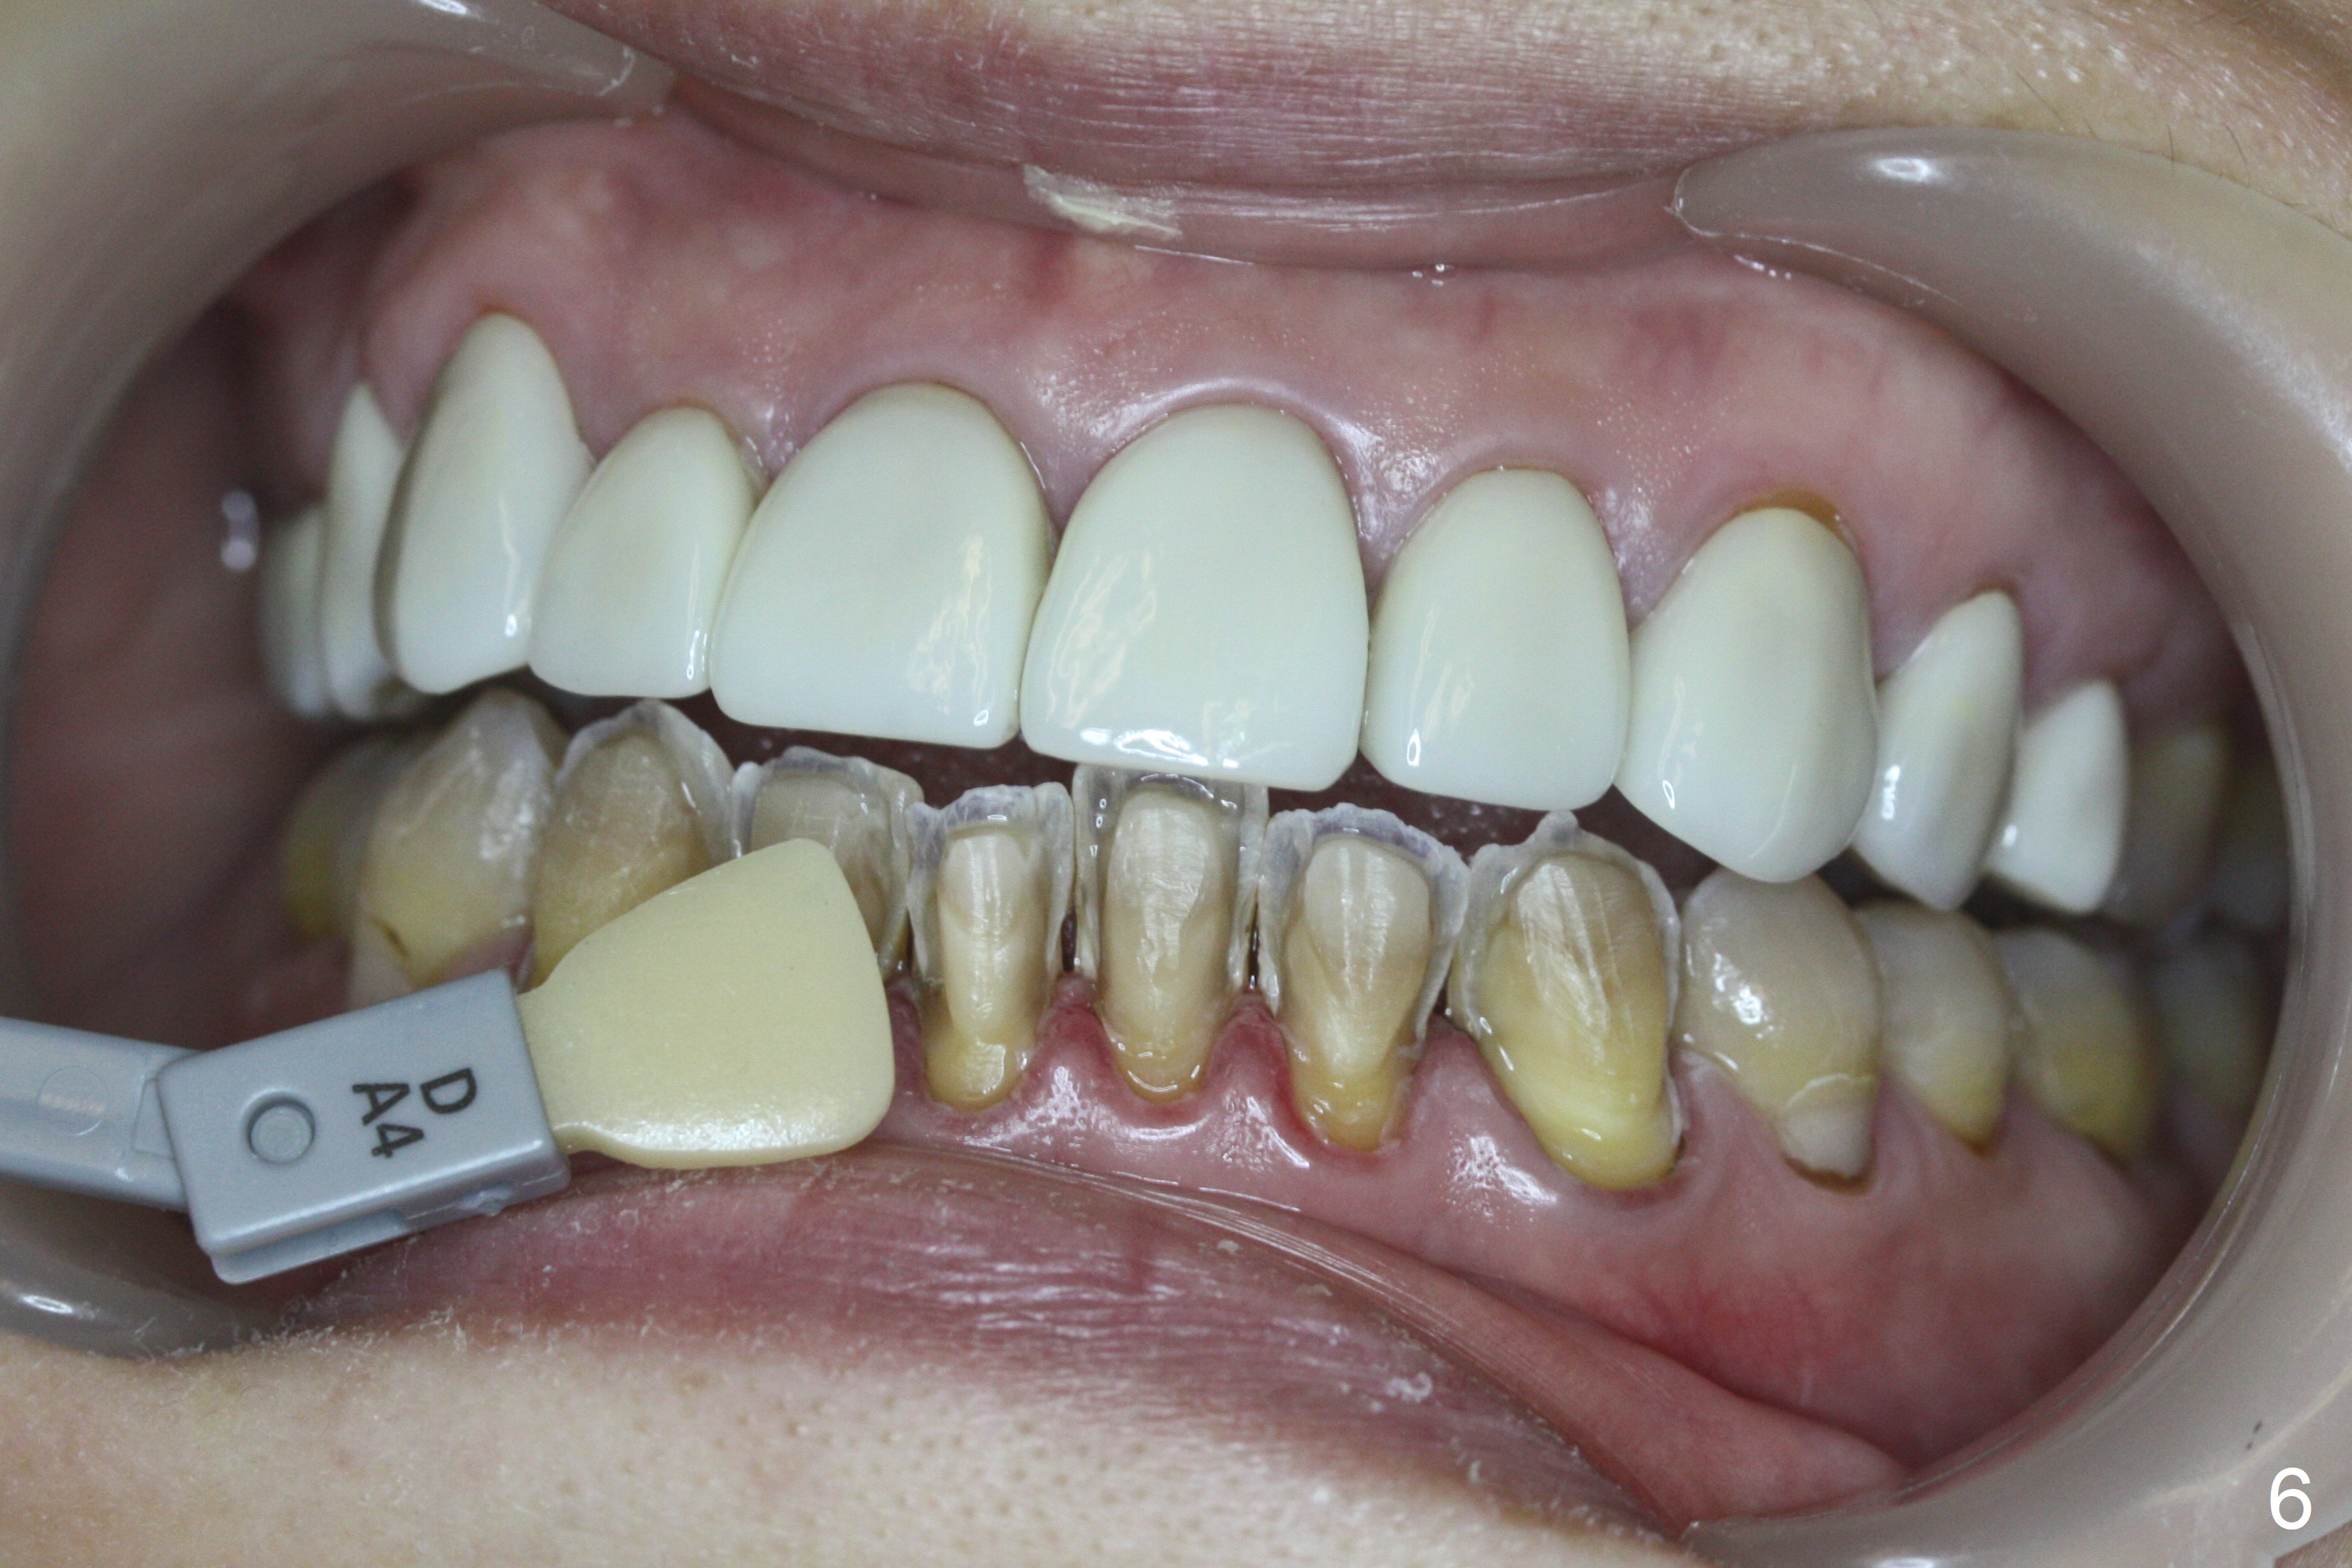

After prep (Fig.5), stump shade is chosen (Fig.6). Although B1 was selected for the upper veneers (Fig.7), the patient prefers to have A1 for the lower ones (Fig.8).